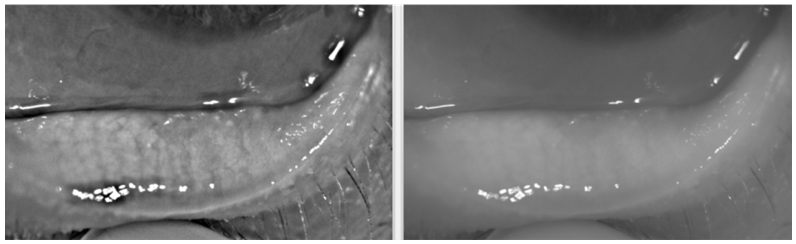

Clinical efficacy was demonstrated by monitoring of patients with dry eye disease with posterior blepharitis (meibomian gland dysfunction - MGD) treated with plasma shock. Immediately after the treatment, the NIKBUT improves (Figure 6). However, during the follow-up period, NIKBUT returns almost to its original value (Figure 7). Other monitored topographic parameters and values in control measurements do not show a statistically significant improvement, except tear meniscus height in temporal region (Graph 1‒3), After the plasma treatment, the condition of the margin of the eyelids is clinically improved mainly due to the liquefaction of the contents of the meibomian glands and easier expression of their contents (Figures 8&9). In 90% of cases in the cohort, there was a subjective improvement (less redness of eyes, less burning, itchy and scratchy, less pain and pulling sensation, less frequency of eye drop dripping) according to the completed questionnaire (DEQ 5). The remaining patients (10%) did not report improvement - their problems were the same as before treatment, they had to further heat the eyelids with warm compresses and leave one frequency in the dripping eye drops. No patient had an exacerbation of pre-existing problems. In some patients, treatment contributed to the discontinuation of previous topical steroid therapy. The limitation of our work is a small group of patients and a short follow-up period.

Figure 8 The condition of the margin of the eyelids is clinically improved after the treatment.

Figure 9 The condition of the margin of the eyelids is clinically improved after the treatment.